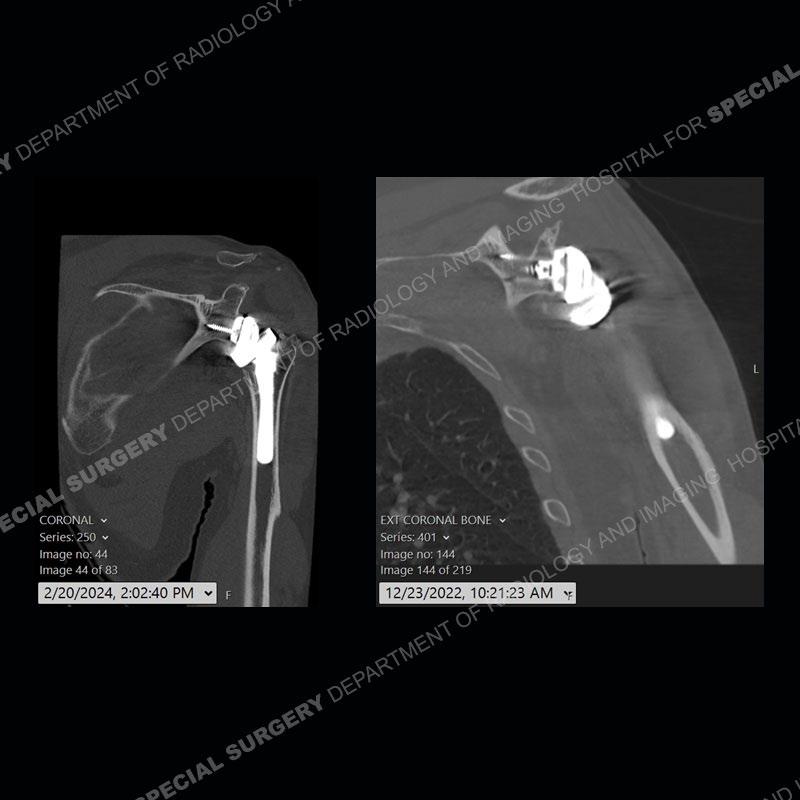

When comparing the radiographs, there is a slight change in the alignment in the components of the prosthesis. On the current radiographs, a radiolucent, crescentic focus is present at the level of the glenoid. When comparing the CT exams, there is a change at the alignment of the glenosphere and the humeral component and now a direct apposition of the components. On the current CT, the radiolucent, crescentic focus is again identified.

If comparison radiographs are present, subtle changes can be made more apparent. Instead of a space between the glenosphere and the humeral tray, there is a direct contact, and there may be an overall change in the alignment at the articulation. The displaced, radiolucent polyethylene liner depending on location can be seen on the radiographs, as in this case. At times, the liner may overlie other structures making identification very difficult on radiographs, but it should almost always be able to be identified on CT (as shown in this example as well). This patient is scheduled for revision procedure.